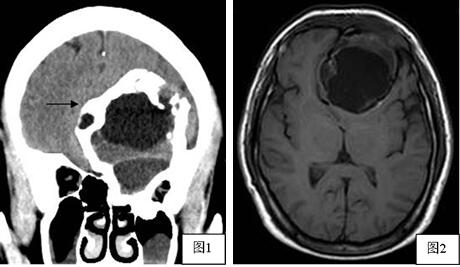

头颅CT(图1)示左前颅窝底一较大占位病灶,大小约7.05cm×5.20cm×7.27cm,边缘见高密度硬化边(图1箭头),其内密度不均。MRI平扫(图2,3)示左前颅窝底病灶呈囊实混合性,中央囊性区较大,呈不均匀长T1长T2信号,周围实性区大部呈长T1短T2信号,增强(图4)病灶周围呈不规则环形强化,病灶内见分隔,病灶向下累及左侧筛窦,向上向后推挤左侧额叶,病灶边界清晰,周围受压脑实质未见明确水肿信号。影像诊断考虑偏良性病变,骨源性肿瘤可能性大。

图1:冠状位CT平扫:肿瘤内部不同分隔内低密度区密度不一致,边缘见高密度硬化边(细箭头)。

图2:T1WI,病灶呈低信号为主;图3:T2WI,病灶呈高信号为主,边缘示环形极低信号影;图4:T1WI矢状位增强:边缘呈不均匀强化,中心未见强化.